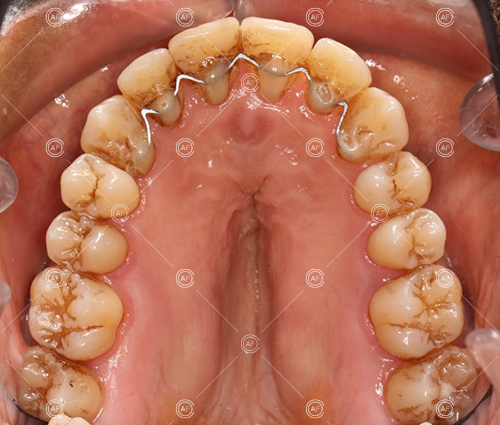

Treatment progressed by starting with thin, flexible nickel titanium archwires of a round diameter, transitioning to a rectangular nickel titanium archwire before eventually working up to a working archwire (1925 stainless steel).

Residual space from the extractions were closed using upper and lower nickel titanium closing coils. Class 2 elastics were used to facilitate space closure in order to gain class 1 buccal segments.

MH debonded in December 2020, with overall treatment time of around 14 months.

She was provided with upper and lower vacuum form retainers, and asked to wear these every night for the first year, and alternate nights for the second year onwards, indefinitely for as long as she wanted her teeth to remain straight. High quality finish was maintained at one year post-debond.